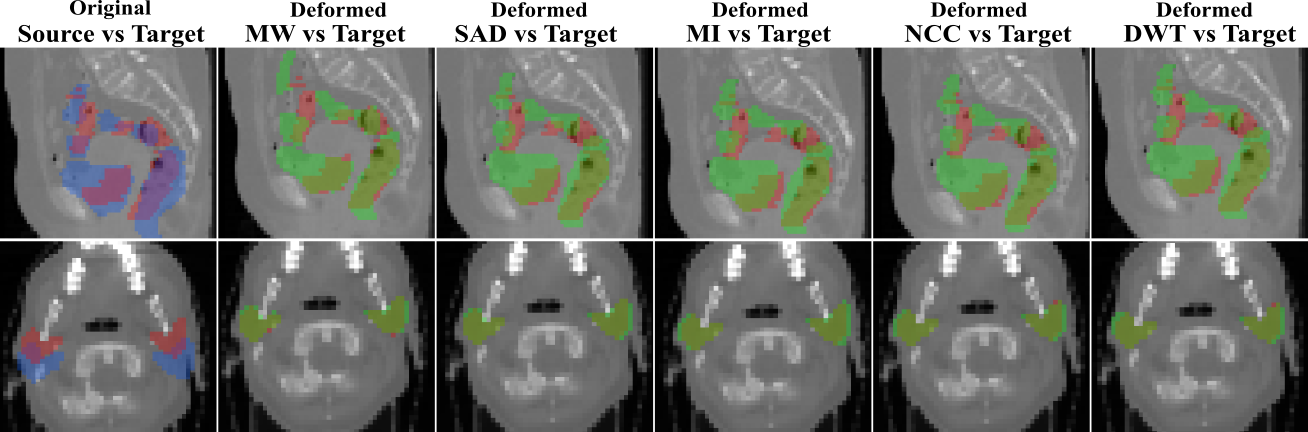

Refer to caption

Figure 4: Overlapping of the segmentation masks in different views for one registration case from RT Abdominal (first row) and RT Parotids (secibd row) datasets (views are different than those shown in the main paper). The first column corresponds to the overlapping before registration between the source (in blue) and target (in red) segmentation masks of the different anatomical structures of both datasets. From second to sixth column, we observe the overlapping between the warped source (in green) and the target (in red) segmentation masks, for the multiweight algorithm (MW) and for the single metric algorithm using sum of absolute differences (SAD), mutual information (MI), normalized cross correlation (NCC) and discrete wavelet transform (DWT) as similarity measure. We observe in a qualitative way that multiweight algorithm gives a better fit between the deformed and ground truth structures than the rest of the single similarity measures, which are over segmenting most of the structures showing a poorer registration performance. This is coherent with the numerical results reported in Figures 2 and 3 from the main paper.